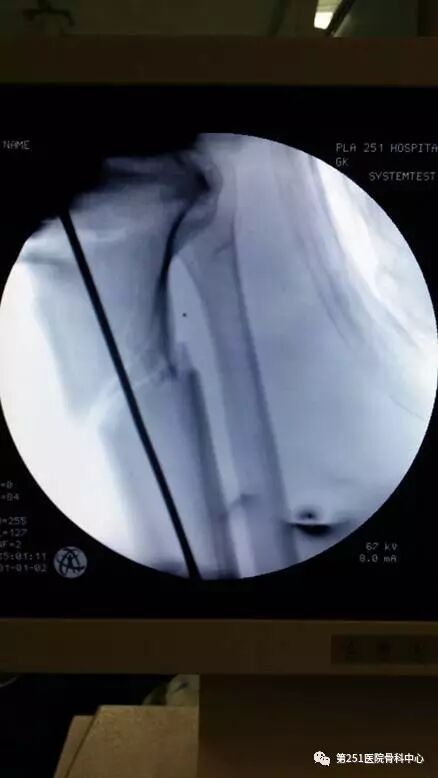

病例8:男性,24岁,车祸伤,胫腓骨近段粉碎性骨折。

![]()